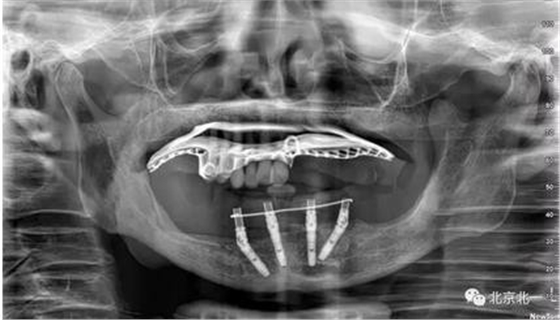

術(shù)前導(dǎo)板設(shè)計(jì),CBCT掃描,制作定位導(dǎo)板1

制作第二副備洞導(dǎo)板, 和第一幅是不同的。